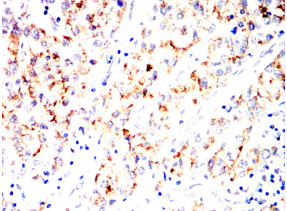

IHC    1/200 - 1/1000